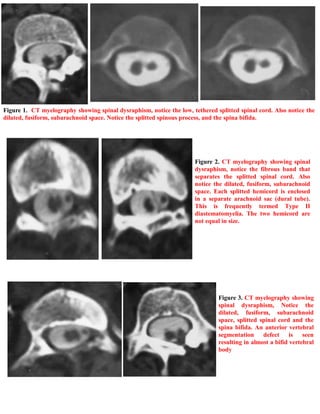

A 11-year-old male patient presented with shortness of the left leg, scoliosis, pes cavus, and an ulcer on his left foot. Examination revealed hair growth on his lower back. He was diagnosed with spinal dysraphism, a type II diastematomyelia, and a low tethered spinal cord based on CT myelography findings of a split, low-lying spinal cord within a dilated fluid space. The document provides information on accessing additional case publications and references a textbook on neuroradiology.